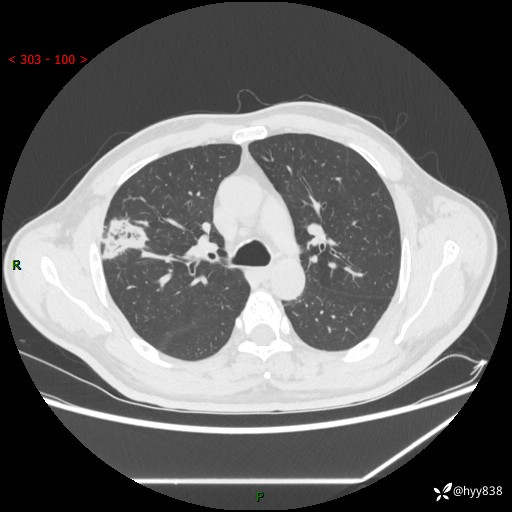

中年男性,体检发现肺占位2天。节段性实变,蜂窝样改变---结果公布~

现病史:患者2天前体检完善胸部CT提示:右上肺团块影,炎症可能,肿瘤性病变不除外,冠状动脉钙化,无咳嗽、咳痰,无寒战发热,无恶心、呕吐等其他特殊不适,未予以特殊治疗,现为明确病变性质来我院就诊,门诊以“肺肿物性质待查”收入我科。 起病以来,患者精神、饮食、睡眠可,大小便正常,体力体重较前无明显变化。

胸部CT平扫+增强